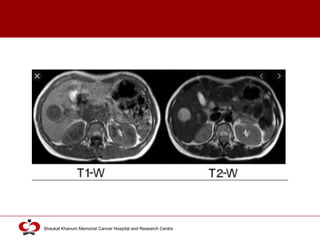

MRI

 More accurate than other imaging techniques

 HCC vs other liver tumors (> 2cm)

 T1- and T2-weighted images

 Early, intermediate and late phases (gadolinium)

 Features:

 Mosaic shape structure

 Capsule

 Early uptake and late washout

 Gd-EOB-DTPA

 liver specific MR contrast medium

 Accumulates in Kupffer cells (phagocytosis) or hepatic cells

 Increased MRI accuracy

T1 weighted T2 weighted

Hypodense Hyperdense 54 % cases

Hypodense Hypodense 16 % cases

Hyperdense Fatty/copper/glycogen infiltration of tumor